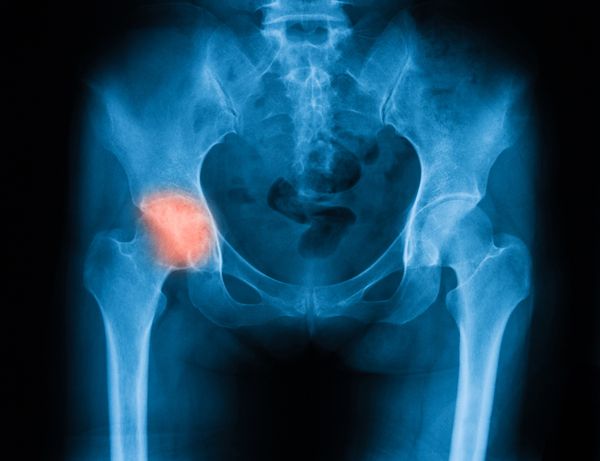

Coxarthrose des Hüftgelenks

Coxa ist die medizinische Bezeichnung des Hüftgelenks. Hier lokalisierte Arthrosen sind in der Mehrzahl der Fälle Folge angeborener Fehlstellungen mit Hüftgelenkluxationen und Hüftkopfnekrosen (Morbus Perthes). Schwere Beine und Schmerzen beim Laufen und in der Leiste sind hierfür charakteristisch. Hinzu kommen infolge der Schonhaltung Schmerzen im Kniegelenk. Sie führen zu erheblichen Einschränkungen in der Beweglichkeit des Beines.

Nur eine frühe Diagnose kann Arthrose verhindern

Angeborene (kongeniale) Fehlstellungen sind in einem möglichst frühen Stadium zu diagnostizieren. Nur so lassen sich Arthrosen durch physiotherapeutische Maßnahmen und Spreizhöschen verhindern. Daher ist eine Ultraschalluntersuchung des Beckens bei Kleinkindern im ersten Lebensjahr Pflicht.